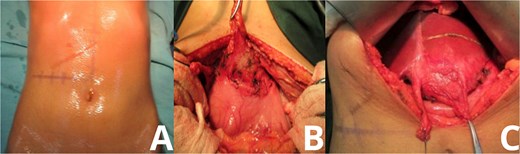

The mass measured approximately 10 cm and, upon resection, was found to contain retained surgical gauze consistent with a textiloma. The rest of the intra-abdominal cavity was explored and found to be unremarkable (Fig. 3).

Gross specimen of explanted gossypiboma. Post-resection images of the excised mass show its characteristic features. (A) Lateral view displays the fibrotic outer capsule enveloping the retained surgical sponge. (B) Opposing view highlights the gauze fibers and associated tissue reaction, confirming the diagnosis of textiloma upon histological examination.

Histological analysis confirmed the presence of a foreign body granulomatous reaction surrounding cotton fibers, consistent with a retained surgical sponge. No signs of malignancy or abscess formation were observed. The patient’s postoperative course was uneventful. She had no signs of infection, no bile leakage, and was discharged with instructions for regular follow-up. At her one-month postoperative visit, she had resumed daily activities with no further complaints.